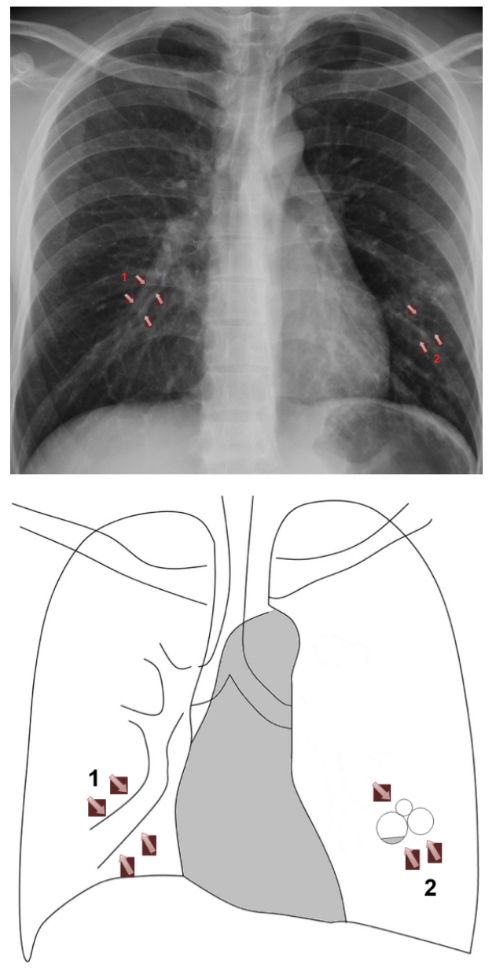

小時候曾因肺炎住院數次。此次理學檢查肺部有囉音,咳嗽後會消失;胸部X光片顯示

雙側肺底部有平行的線狀陰影(tram-track markings)。其最有可能的診斷為?

1. 整個下肺野的肺紋變多(increased lung making)、變密集。

2. 支氣管壁增厚或擴張,當擴張的支氣管中含有空氣時,其增厚的管壁,側面(en profile)會看到呈二條平行的線狀陰影(tram track sign),正面(en face)會看到環狀陰影(ring shadow),當擴張的支氣管充滿fluid,在影像下會看到支氣管變不透亮或看到一些氣-液界面air-fluid levels。

3. 受侵犯肺葉幾乎都會喪失容量(volume).